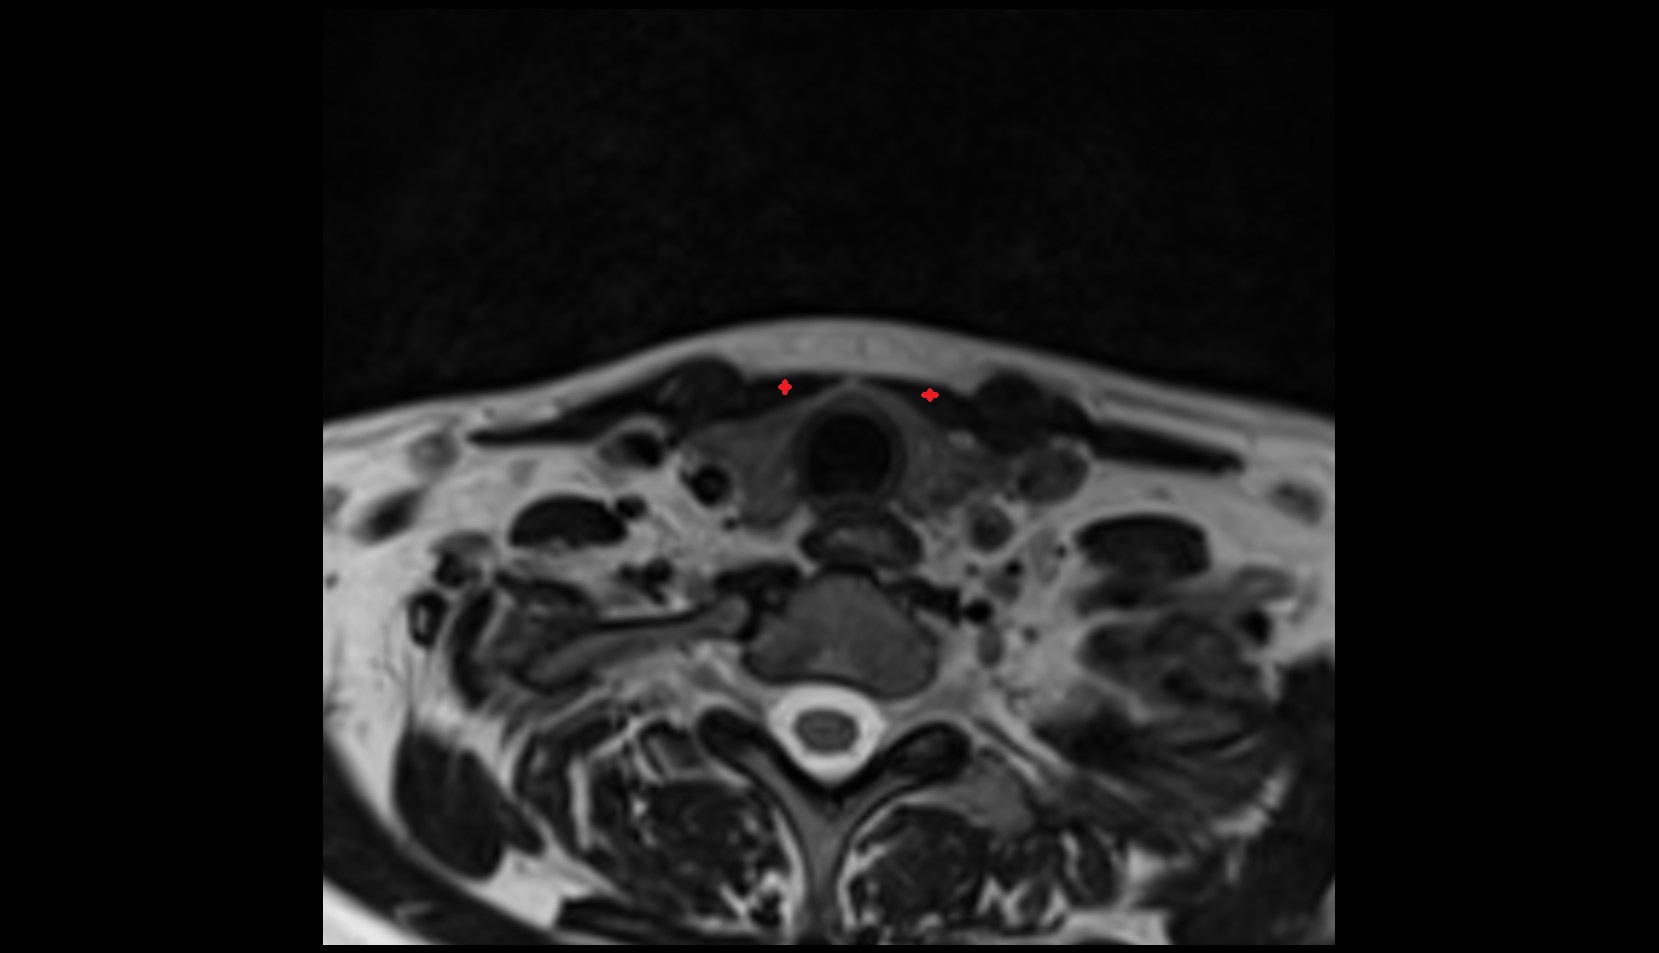

- Peripheral zone of prostate

- Anterior Fibromuscular Stroma of prostate

- Central zone of prostate

- Transitional zone of prostate